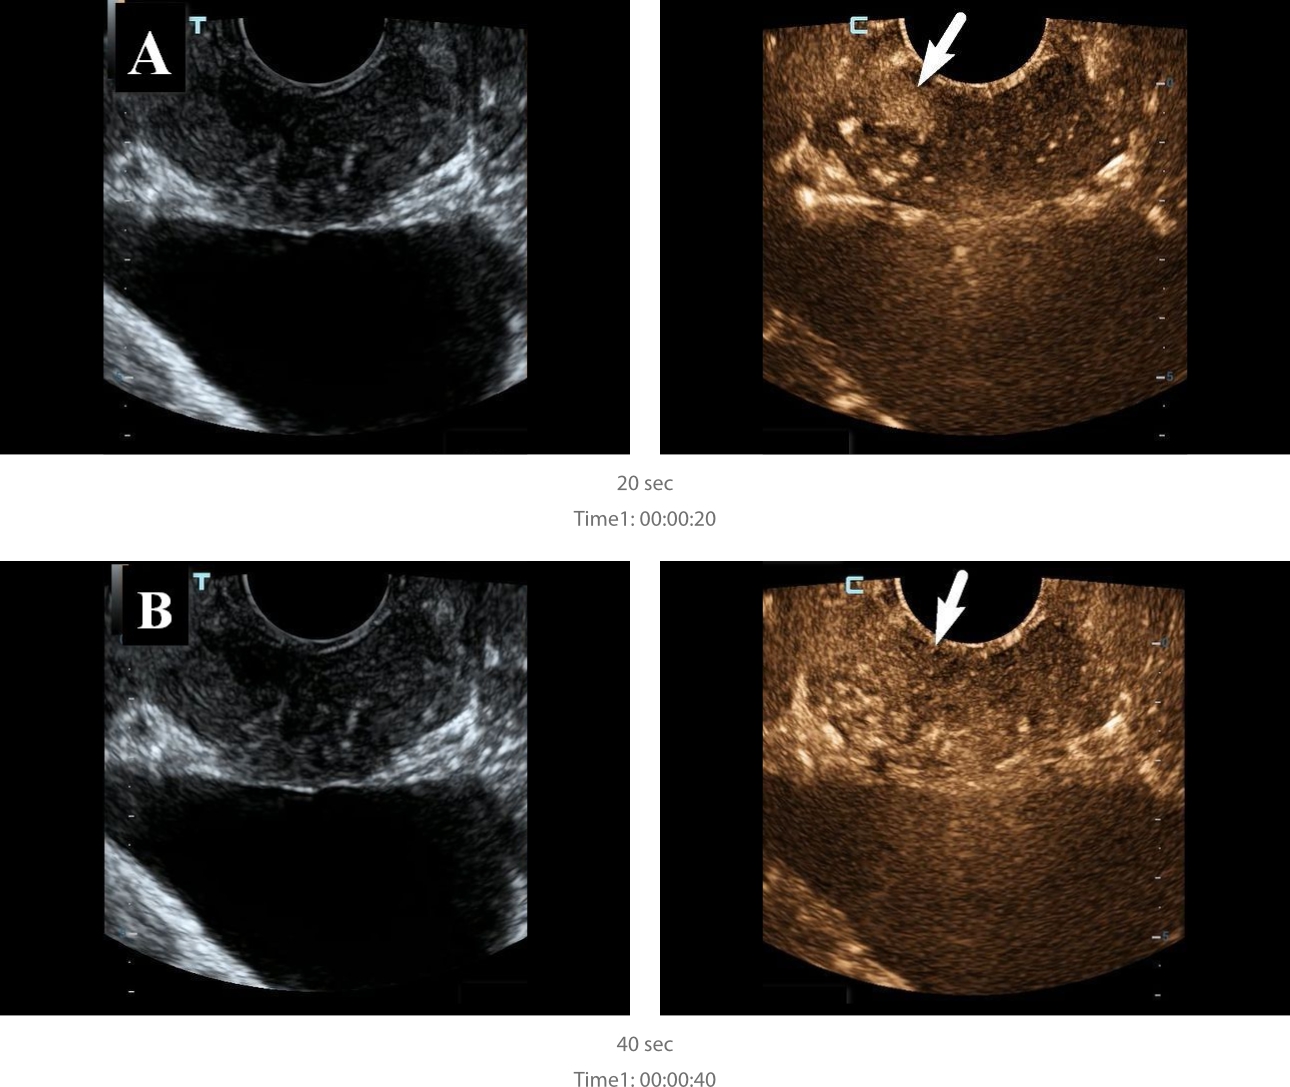

Contrast Enhanced Ultrasound Findings

For contrast enhanced ultrasound (CEUS), the area of interest was visualized immediately after injection of 2.4 ml of Sonovue (Bracco Swiss, SA, Switzerland) for 3 minutes in contrast mode. The hypoechoic lesion in the peripheral zone was shown to have hyperintensive contrast enhancement of relatively unchanged parenchyma, with rapid influx and outflow of contrast medium (Fig. 4).